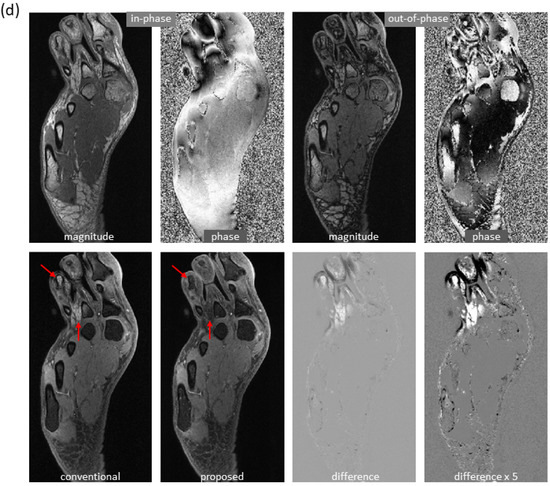

Figure 6 shows the mitigation of severe artifacts induced by a metallic object, further demonstrating robustness to out-of-distribution data. The dramatic changes in local magnetic fields made the cases with metallic implants very challenging. In a knee study (Figure 6a), phase corruption in dual-echo images caused severe artifacts in the reference water/fat images. Interestingly, the predicted images lacked these artifacts. Here, the test images were acquired on a PET-MRI scanner (whereas the majority of training data were obtained on MRI scanners). In an ankle case (Figure 6b), both signal loss and phase corruption were observed in dual-echo images, leading to artifacts in the reference images. The metal artifacts, along with additional water/fat swaps that occurred in peripheral region of off-isocenter slices, were corrected in the predicted images even though the ankle images were acquired on a 1.5T MRI scanner (while training data were obtained on 3T scanners). Of note, for these two cases, is the fact that the training sets lacked any examples with metallic implants.

Figure 6. Marked reduction of metal-induced artifacts, where the training set lacked any examples with metallic implants. (a) In this knee case acquired on a PET-MRI scanner, severe off-resonance artifacts occurred in the reference images since the local magnetic field near metal changed dramatically (as can be seen from the input phase images). In the predicted images, metal-induced artifacts were largely corrected. (b) In another ankle case acquired on a 1.5T MRI scanner, signal loss (blue arrow) and phase corruption (red arrow) were observed in the input images, resulting in artifacts in the reference images (yellow arrow). In addition, severe water/fat swaps (green arrow) occurred in the peripheral region of this off-isocenter slice. Both metal artifacts and water/fat swaps were mitigated in the predicted images, even when the model was trained with only knee images acquired on 3T scanners.